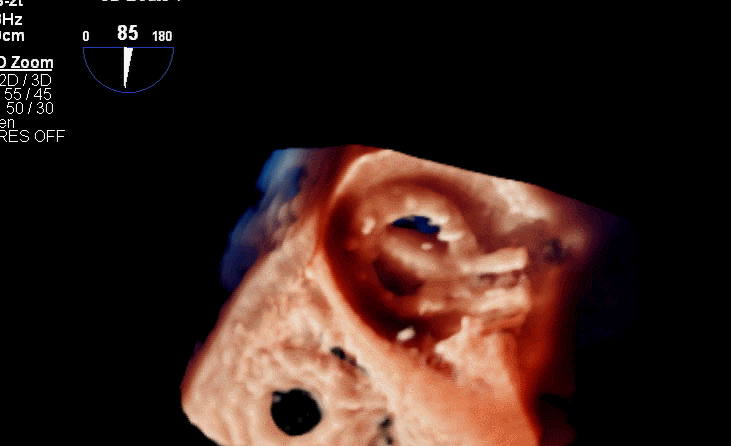

食道超声评估

三尖瓣术前平均压差9mmHg

三尖瓣瓣中瓣术后平均压差3mmHg

术后TV生物瓣活动良好

术后三维超声同时显示MV机械瓣及新的TV生物瓣